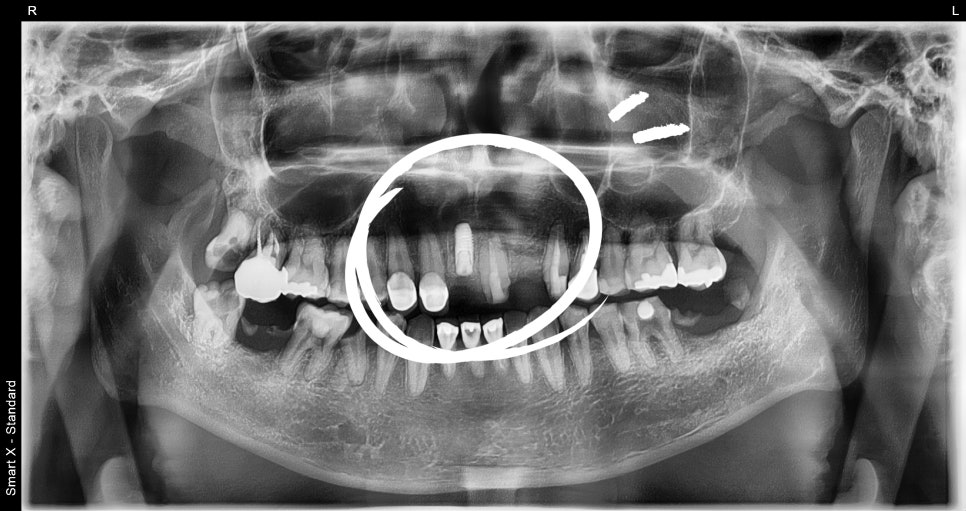

① #11번 치아 발치 및 낭종 제거 수술

– 발치와 동시에 2cm낭종 병소를 완전 제거했습니다.

– 낭종으로 인해 흡수된 뼈 부위에 동종골 이식을 병행했습니다.

② 당일 임플란트 식립

– 뼈 상태를 면밀히 확인한 후 즉시 식립 가능한 깊이와 방향으로 수술을 진행했습니다.

– 해부학적으로 중요한 앞니 부위인 만큼 정밀한 각도와 깊이 조절이 필요했습니다.

📸 수술 후 X-ray

– 병소 완전 제거 및 임플란트 식립

– 이식재로 뼈 높이 확보